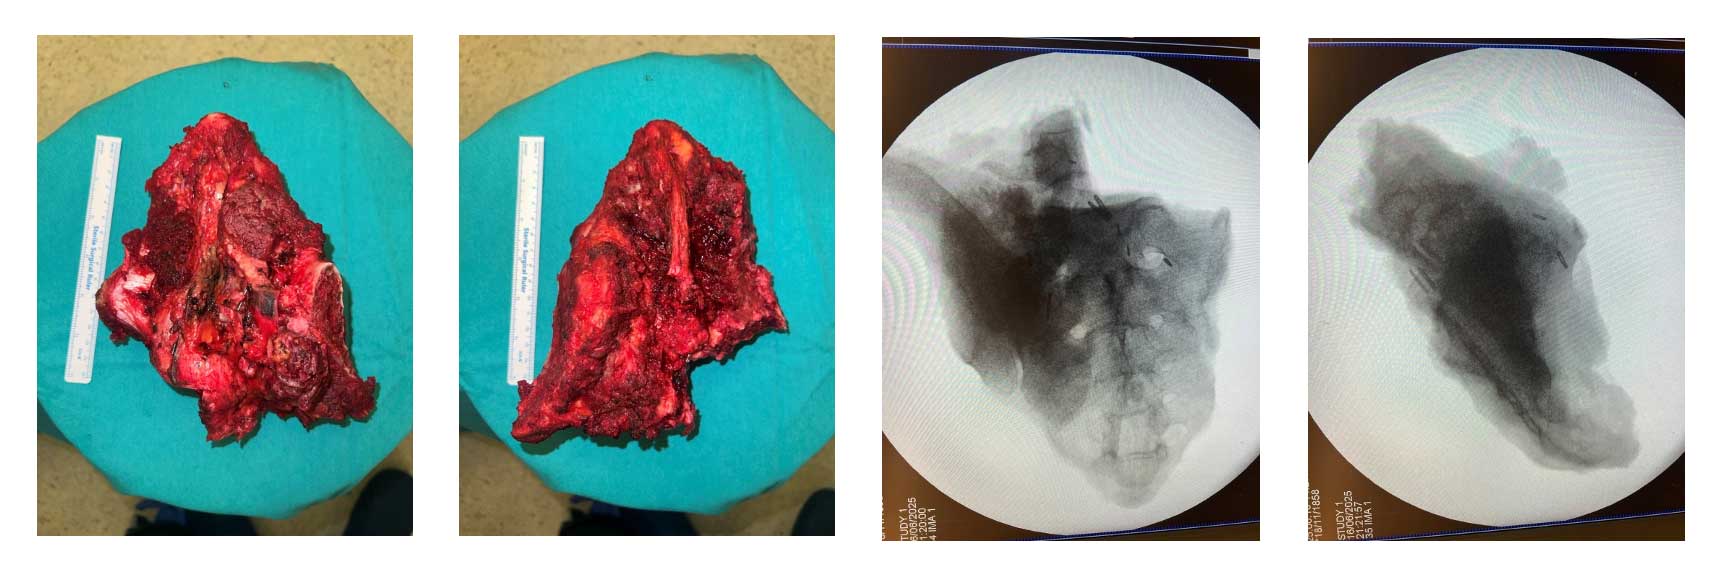

Ameliyat Esnası: Rezeksiyon dokusunun klinik ve skopi görüntüsü

Ameliyat esnası ve sonrası: Total sakrektomi sonrası fibula, titanyum kafesler ve lumbopelvik fiksasyon ile yapılan rekonstrüksiyon işleminin klinik ve röntgen görüntüsü.